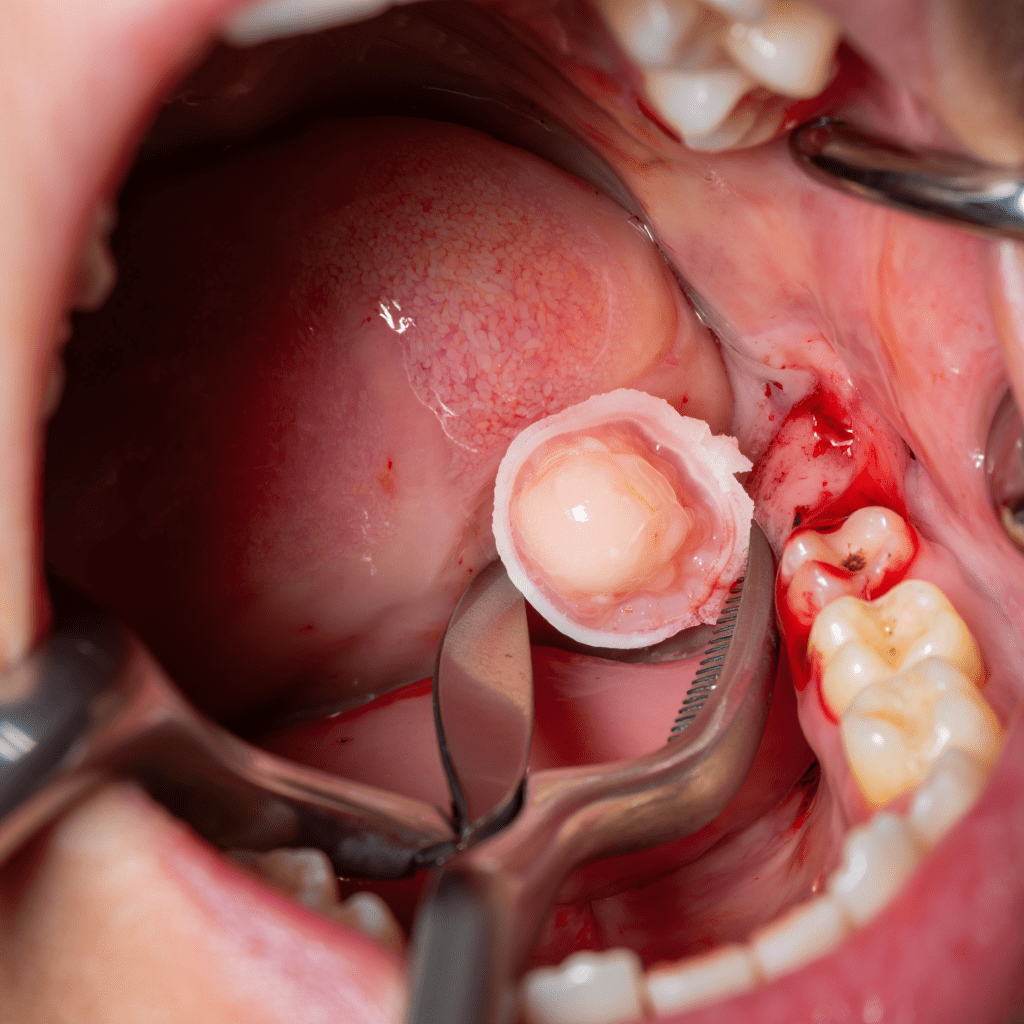

Çene Kisti Operasyonları

Çene kisti, çene kemiği veya ağız içindeki yumuşak dokularda oluşan, genellikle gömülü dişler, enfekte diş kökleri veya gelişimsel anormalliklerin çevresinde ortaya çıkan sıvı dolu keseciklerdir. Çoğu kist iyi huyludur ancak tedavi edilmezse sessizce büyüyerek ciddi hasarlara yol açabilir. Girne’de Dental Options Diş Kliniği olarak, çene kistlerinin güvenli ve etkili cerrahi yöntemlerle çıkarılmasını sağlıyoruz.

Kliniğimizde, çene kisti ameliyatları son teknoloji dijital planlama araçları ve modern tekniklerle hassas şekilde gerçekleştirilir. Kist tespiti görüntüleme sırasında rastlantısal yapılabilir ya da belirtilerle başvurabilirsiniz; deneyimli cerrahi ekibimiz güvenli, etkili ve konforlu bir tedavi sunar.